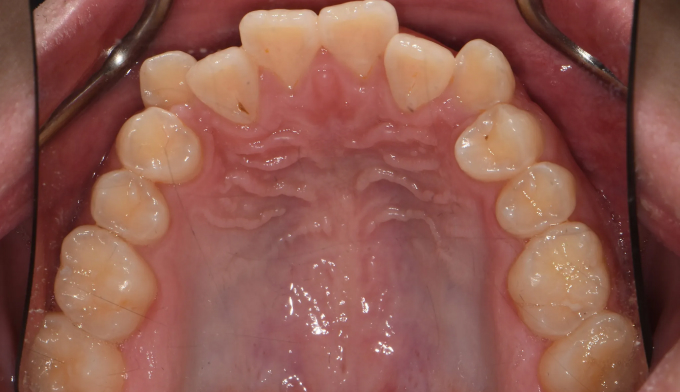

주걱턱 경향을 갖는 청소년들은 개방교합과 덧니를 동시에 갖는 경우가 많습니다. 아래턱의 과도한 성장은 혀의 위치를 아래로 처지게 만들고, 이는 위턱의 폭을 줄어들게 만들어 덧니가 생기기 쉽게 만듭니다. 그리고 과도한 아래턱의 성장은 앞니의 교합을 벌어지게 만들어 개방교합 또한 나타나게 됩니다.

그 정도에 따라 발치가 필요한 경우도 있지만, 성장기의 청소년의 경우에는 최대한 발치 없이 자연스러운 치열과 입매를 만드려고 합니다.

좁아진 위턱 악궁을 확장시켜서 치아를 배열시키고, 과도하게 앞으로 나온 앞니를 미니스크류를 이용하여 후방이동 시킵니다.

총 치료기간은 24개월 소요되었습니다.

남자아이들의 경우에는 성장이 고등학교 이후에도 지속되는 경우가 많으므로 치료 이후에도 주기적으로 성장을 관찰하여야 합니다.